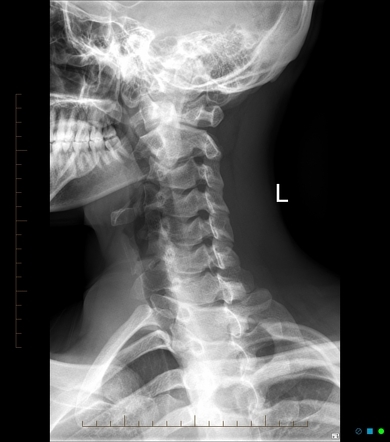

C-Spine: lateral + open mouth peg view

what to asses in c spine radiograph?

Adequacy: must see C7-T1 junction

Alignment:

ant vertebral bodies

ant vertebral canal

post vertebral canal

tips of spinous processes

Bones: shapes of bodies, laminae, processes

cartilage: Intervertebral discs should be equal height

Soft tissue